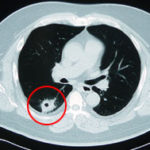

胆管がんや胆嚢がんの治療においては、主に外科的手術・放射線療法、化学療法(抗がん剤等)などの治療が柱となりますが、胆管がんや胆嚢がんは手術を行っても再発率がとても高いですし、見つかったときには手術が出来ないほど進行している事も多く決して予後の良い病気ではありません。

放射線療法や化学療法(抗がん剤治療)も非常に効きにくいことが胆管がん(胆管癌)/胆嚢がん(胆嚢癌)の治療を困難なものにしています。